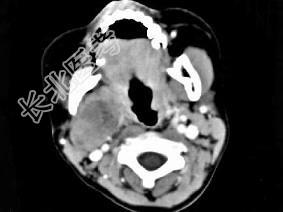

- 单项选择题女,4岁, 右侧颈部可扪及一包块约两个月,无热无痛, CT如图所示,最可能的诊断为 ( )

A、咽旁血管外皮瘤

B、咽旁副神经节瘤

C、咽旁脓肿

D、咽旁神经纤维瘤

E、咽旁小唾液腺混合瘤